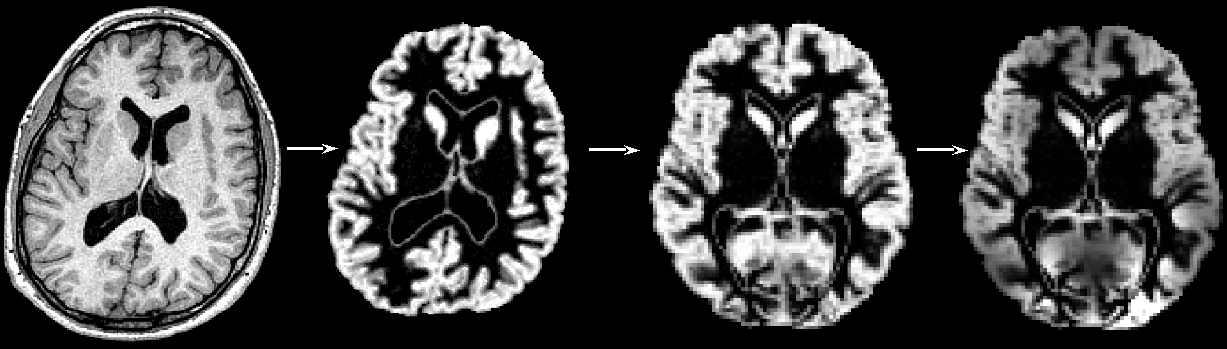

"Structural data was analysed with FSL-VBM (Douaud et al., 2007, https://fsl.fmrib.ox.ac.uk/fsl/docs/structural/fslvbm.html), an optimised VBM protocol (Good et al., 2001) carried out with FSL tools (Smith et al., 2004). First, structural images were brain-extracted and grey matter-segmented before being registered to the MNI 152 standard space using non-linear registration (Andersson et al., 2007). The resulting images were averaged and flipped along the x-axis to create a left-right symmetric, study-specific grey matter template. Second, all native grey matter images were non-linearly registered to this study-specific template and "modulated" to correct for local expansion (or contraction) due to the non-linear component of the spatial transformation. The modulated grey matter images were then smoothed with an isotropic Gaussian kernel with a sigma of ?? mm. Finally, voxelwise GLM was applied using permutation-based non-parametric testing, correcting for multiple comparisons across space."

First, all brain-extracted images are segmented into GM, WM and CSF. Then, GM images selected in the template_list file (*_struc_GM) are affine-registered to the GM ICBM-152 template, concatenated and averaged. This averaged image is then flipped along the x-axis and the two mirror images then re-averaged to obtain a first-pass, study-specific "affine" GM template ("template_GM_init"). Second, the template_list GM images are re-registered to this "affine" GM template using non-linear registration, concatenated into a 4D image called "template_4D_GM", averaged, flipped along the x-axis. Both mirror images are then averaged to create the final symmetric, study-specific "non-linear" GM template at 2x2x2mm3 resolution in standard space.